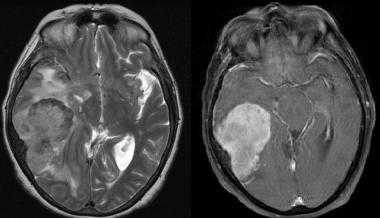

Менингиома височной области. На серии последовательных МР-изображений видно крупное образование правой височной области с паттерном контрастирования по типу «колеса со спицами», местным объемным воздействием, отеком окружающих тканей и гиперостозом подлежащей кости.

Менингиома теменной области. МР-изображения, полученные с использованием следующих последовательностей: аксиальное Т2-взвешенное, аксиальное Т2-взвешенное, корональное FLAIR -изображение и сагиттальное Т1-изображение. Крупная левосторонняя менингиома выглядит в виде экстрааксиального образования с паттерном «колеса со спицами» и отеком окружающих тканей.